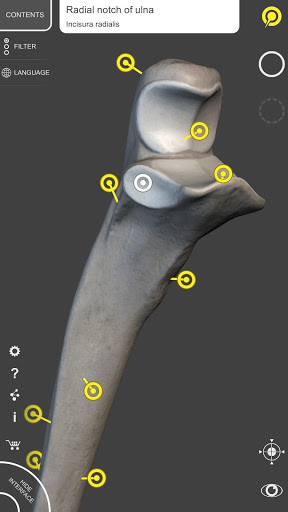

Each bone of the human skeleton has been reconstructed in 3D, you can rotate and zoom in on each model and observe it in detail from any angle.

By selecting models or pins you will be shown the terms related to any specific anatomical part, you can select from 12 languages and show the terms in two languages simultaneously.

• Accurate 3D modeling

• Surfaces of the skeleton with high resolution textures up to 4K

• Rotate and Zoom every model in the 3D space

• Interactive Pin allow visualization of the term relative to every anatomical detail